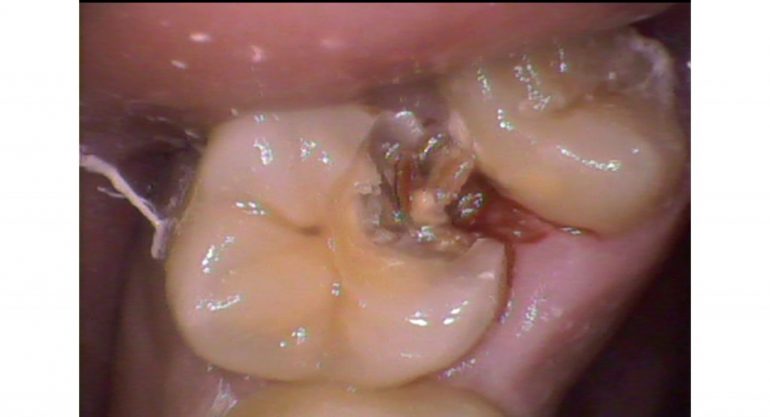

丸の部分を黒いところが問題

(虫歯の取り残し)